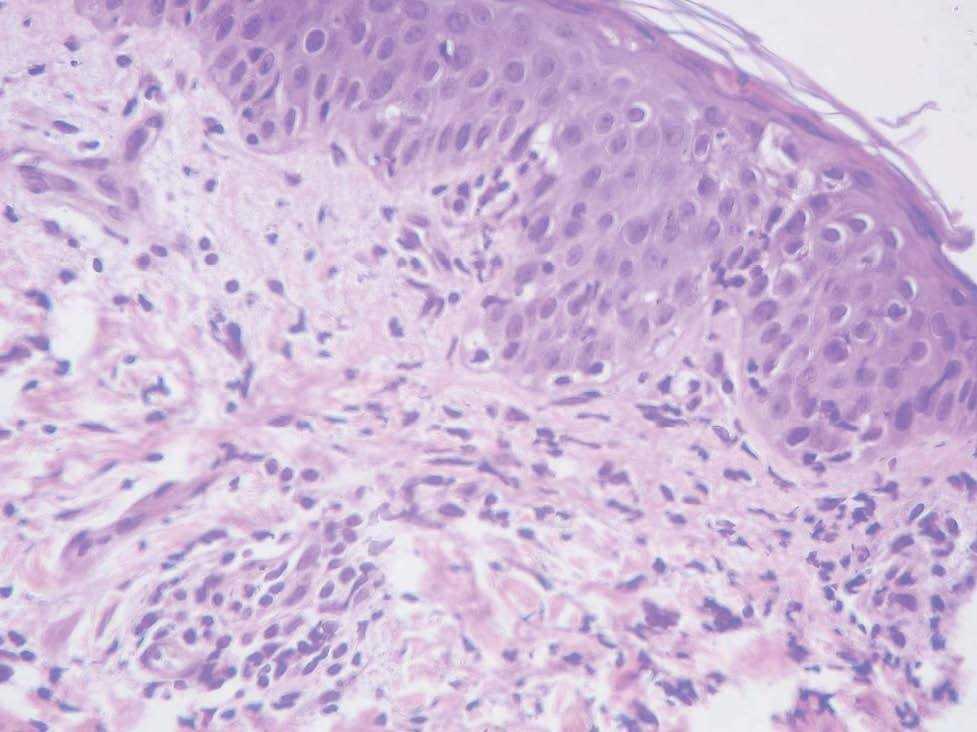

A las 8 semanas del nacimiento, aparecieron en mejillas lesiones anulares eritematoedematosas de bordes no descamativos y en las extremidades se desarrollaron lesiones similares (figs. 4-5). Éstas desaparecieron sin tratamiento en una semana. La histología de los bordes activos reveló una epidermis normal con un infiltrado mononuclear en dermis con aislados eosinófilos (fig. 6). Durante el periodo de resolución de las primeras lesiones, una nueva erupción reticulada apareció en el área del pañal, ingles, hombros, espalda y extremidades proximales. Eran placas anulares atróficas ligeramente descamativas en el borde. La biopsia de estas nuevas lesiones reveló edema en dermis superficial con un infiltrado linfocitario perivascular y perifolicular, con una intensa degeneración vacuolar de la capa basal (fig. 7). Los análisis mostraron AST 75 U/L; ALT 60 U/L; ANA (+) 1/640; anti-Ro (+); anti-ADNds (); anti-U1-RNP (;anti-La (); anti-Sm (), medidos con ELISA. El único tratamiento que se recomendó fue la fotoprotección solar. Las lesiones cutáneas desaparecieron en 2 semanas. A los 10 meses los anticuerpos eran negativos.

Fig. 7.--Caso 3. LEN con afectación epidérmica. Degeneración vacuolar de la capa basal e infiltrado inflamatorio mononuclear en la dermis. (Hematoxilina-eosina, x40.)